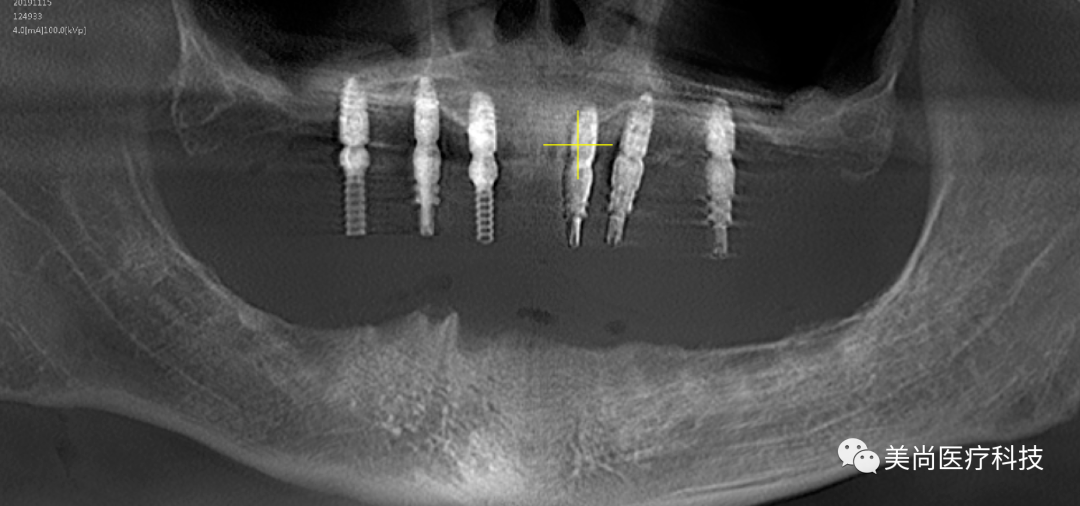

术前X-ray

制作种植导板